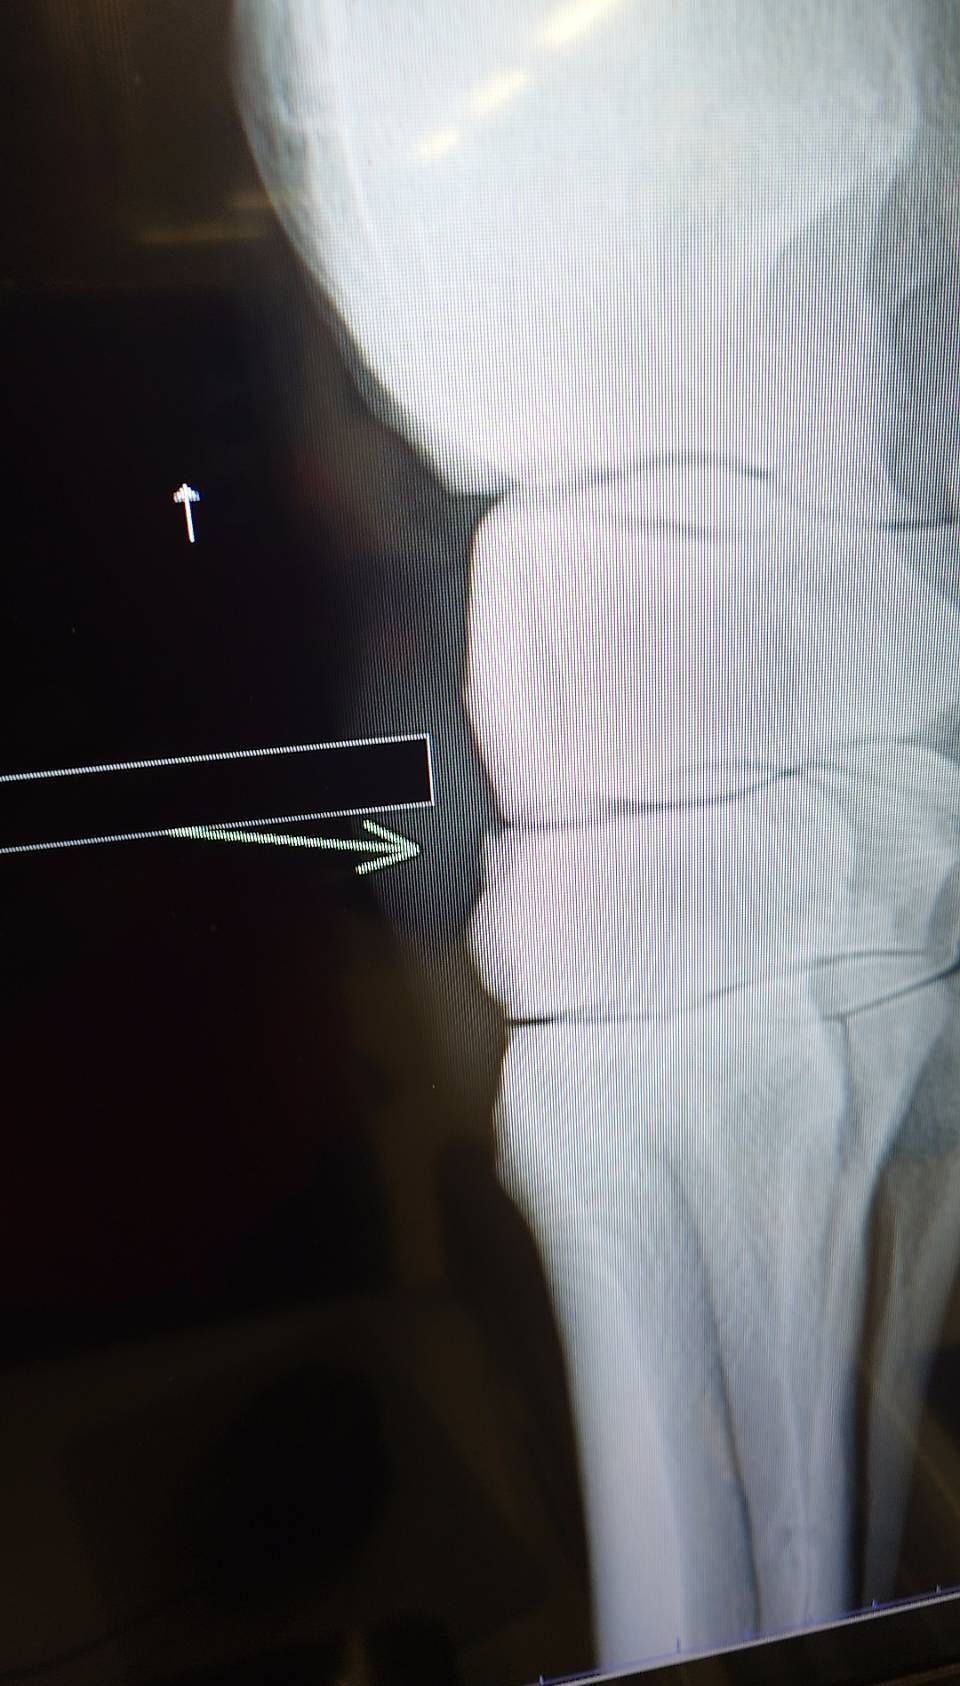

前走で左第3手根骨剥離骨折を発症してしまいました。骨片除去手術を実施し、見舞金9号(競走中6カ月)を適用したうえ、オークション出品となります。

※2026年2月28日の競走で、左第三手根骨剥離骨折を発症。事故見舞金9号(競走中の事故により事故発生の日から6カ月以上出走できなくなった場合)を受給しています。骨片除去手術を実施しています。